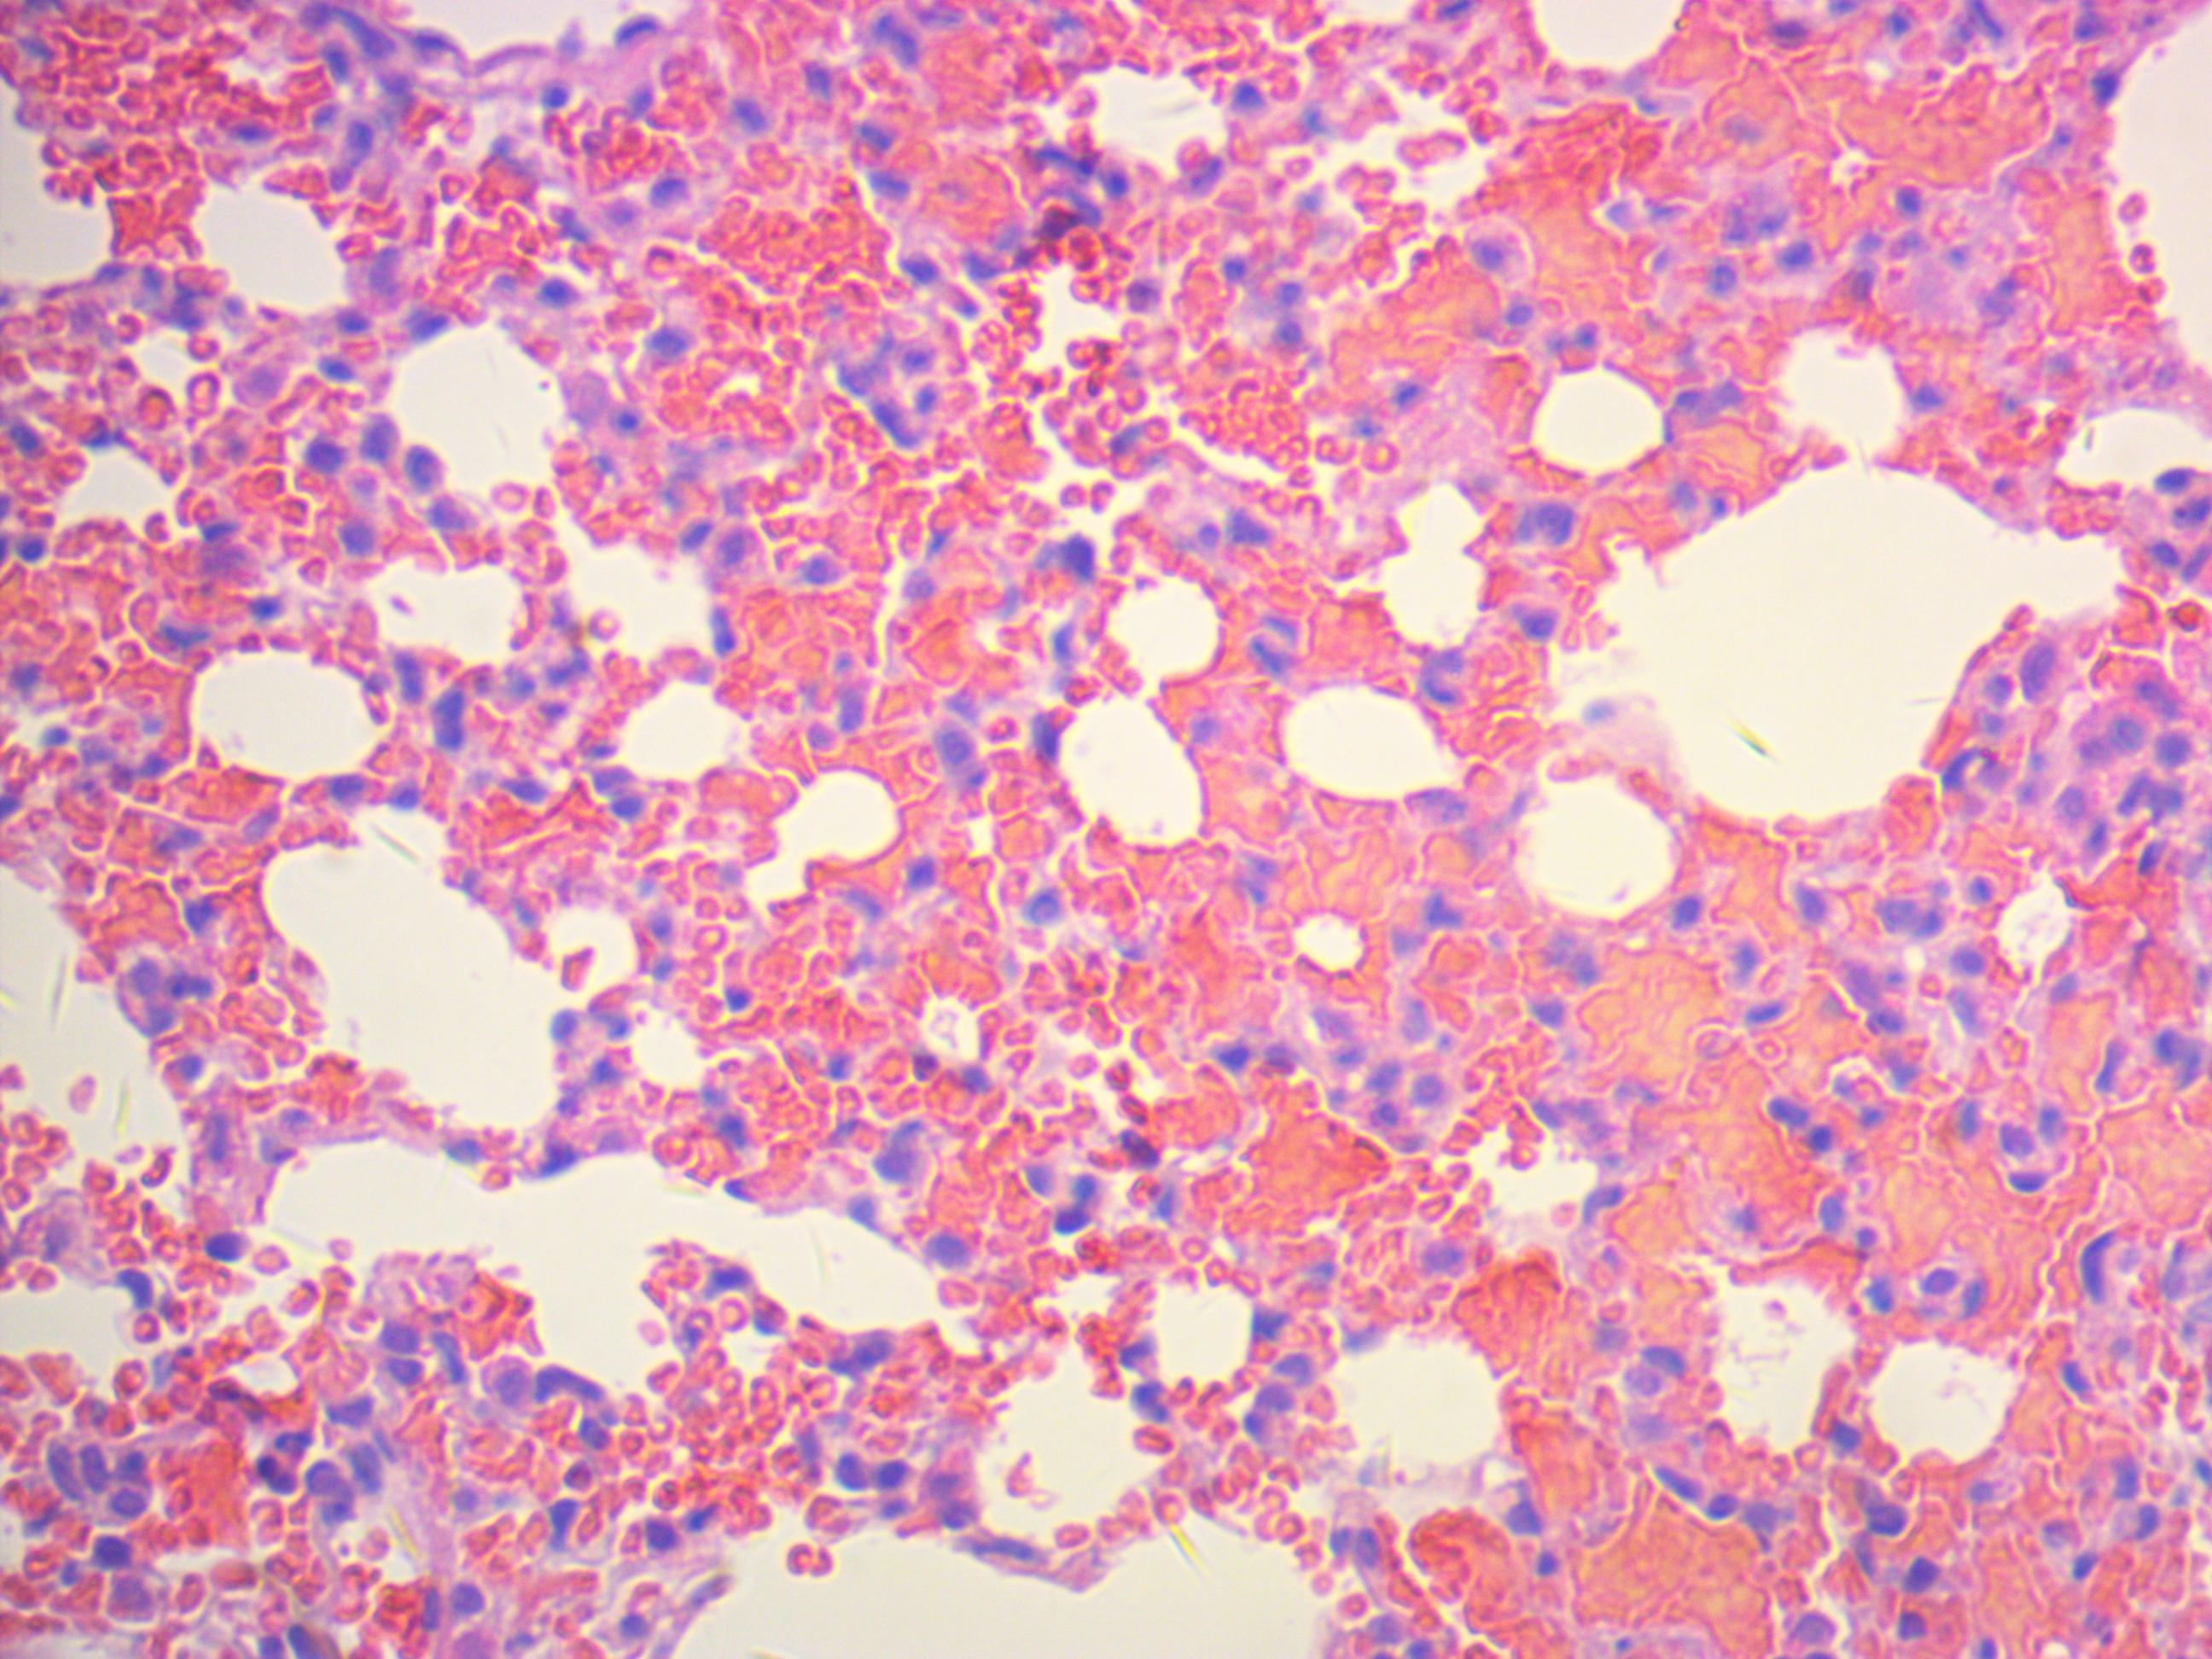

常规(HE)染色技术

常规染色或HE(Haematoxylin and eosin)染色。它是病理技术中最常用的一种方法,通过它可以做出病理诊断和发现寻求别的辅助方法,以达到准确,完整的病理诊断。